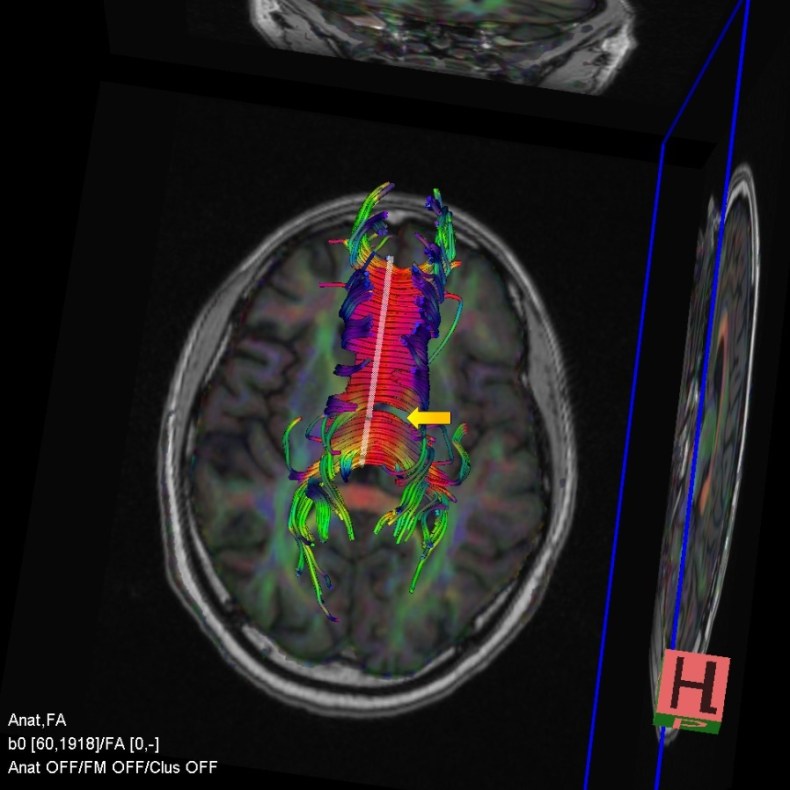

In addition to using tools derived from connectomics, we also have access to advanced imaging technology. Naturally, this comes at an additional fee but can provide extremely valuable information and increases the value of our NICE functional capacity evaluations. (The fee is paid to the radiology department, not us.) Specifically, we are able to commission diffusion tensor images (DTI) that reveal the fibre tracts of the brain. DTI is especially valuable in cases of traumatic brain injury and multiple sclerosis.

For example, Figure 4 is a DTI image. Have a look and notice that there is a break in the patient’s corpus callosum (yellow arrow). That’s the fibre tract that connects the two cerebral hemispheres. DTI uses anisotropy to map fluid flow in neuronal membranes. The colours in the image indicate the direction of flow. Red/pink shows left-right fibre tracts. Green denotes anterior-posterior tracts. Blue shows superior-inferior fibre tracts. Importantly, this break in the corpus callosum was not apparent on a standard MRI. Thus, DTI provides important additional information. In this particular case, this observation was clinically significant and explained various findings on the psychometric tests.